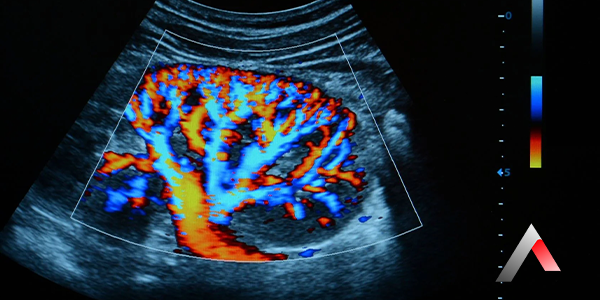

• Renkli Doppler: Kan akışını renkli olarak gösterir. Bu, kan akışının yönünü ve hızını görsel olarak değerlendirmeyi kolaylaştırır. Genellikle kırmızı renk, proba doğru gelen kan akışını, mavi renk ise proptan uzaklaşan kan akışını gösterir.

Renkli Doppler, Doppler ultrasonografinin bir türüdür. Kan damarlarındaki kan akışını renkli olarak göstererek, kanın hangi yönde ve ne hızla aktığını görsel olarak değerlendirmeyi kolaylaştırır.

Renkli Doppler'da, kan akışının yönü ve hızı, farklı renklerle kodlanır. Genellikle kırmızı renk, proba doğru gelen kan akışını, mavi renk ise proptan uzaklaşan kan akışını gösterir. Renklerin parlaklığı, kan akışının hızını gösterir.